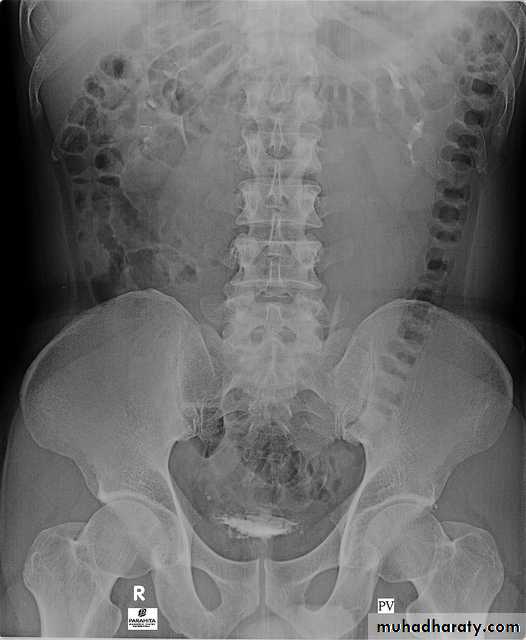

5. A full bladder film (with the urinary bladder fully distended with contrast)

6. Post voiding full length film

4. Bladder

The bladder is a centrally located structure.

Smooth in outline.

Smooth indentation from above by uterus on the right or sigmoid colon on the left and from below by muscles of the pelvic floor is normal.